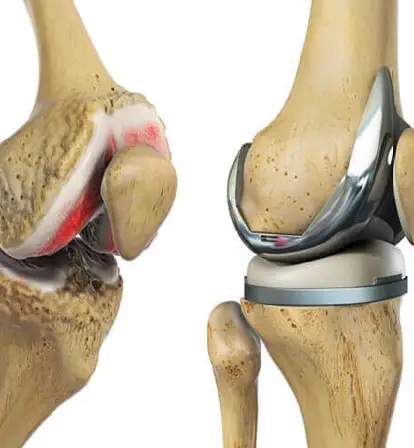

Understanding Total Knee Replacement

Total knee replacement involves removing damaged joint surfaces and replacing them with artificial components to relieve pain, restore function, and improve overall quality of life. It is commonly recommended for patients with severe arthritis, degenerative joint disease, or injuries that limit mobility and daily activities.

Modern TKR surgery incorporates advanced technology, including robotic assistance, to enhance precision and improve the alignment of implants. This ensures better long-term outcomes, helping patients regain strength, flexibility, and confidence in their knees after surgery.

How TKR Surgery Is Performed

TKR surgery involves removing the damaged knee joint surfaces and replacing them with artificial implants that mimic natural movement. Robotic assistance may be used for precise implant alignment, enhancing joint stability and function.